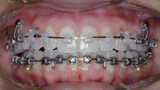

New Age orthodontics and orthopaedics with temporary anchorage devices